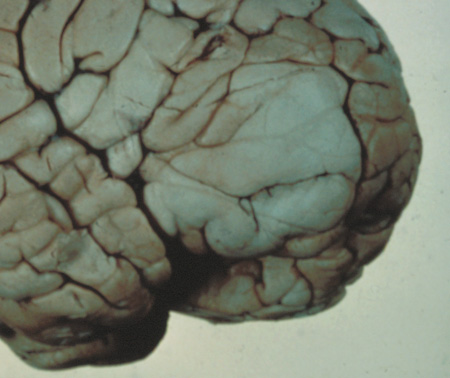

- Cognitive impairment. Thirty percent to 60% of children with NF1 have learning difficulties, which

are typically mild and nonprogressive. These include visual-spatial

problem-solving difficulty, language disorders, and attention

deficit disorder. The reason for this is not clear but may be related

to unidentified bright objects (UBOs) seen on T2-weighted

brain magnetic resonance imaging (MRI) scans. These hyperintensities

are common in young patients with NF1 but decrease with advancing

age. The histopathologic correlate of UBOs is unclear. It has

been postulated that the prevalence of learning difficulties in children

with NF1 may be related to heterozygosity of the NF1 gene (i.e., the gene may have additional functions that affect cognition when the

full complement of its gene product is not expressed in the central nervous

system).25,32–34